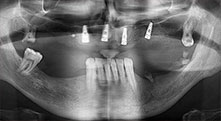

Брату: Ние предпочитаме да използваме техниката "сандвич" за аугментация в страничната долна челюст. Покритие на костта се подготвя с пиезо трион и кресталният фрагмент се фиксира с микровинтове. Поставяме смес от автогенна костна присадка и ксеногенен костозаместител между тях. Това работи много надеждно. Трябва винаги да осигурявате достатъчно оразмерени вертикални срезове при шиниране на алвеоларния гребен в долната челюст. В противен случай, костта лесно може да бъде счупена.